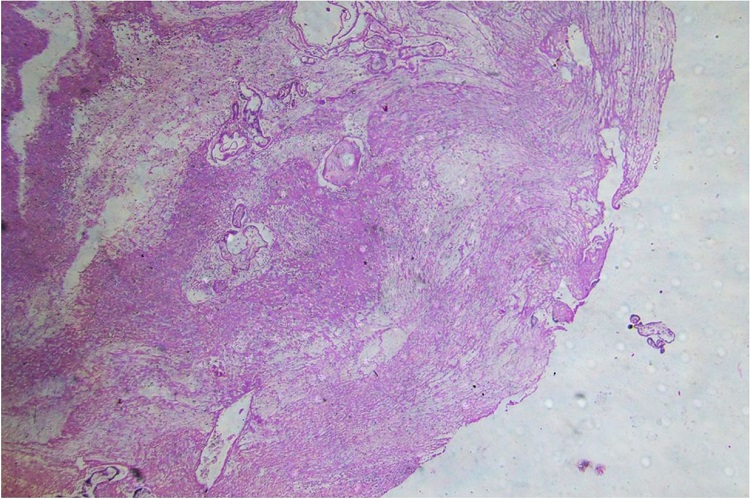

Histological examination of the margins of the perforated uterine wall showed chorionic villi invading the myometrium and serosa breaching the uterine wall (Figure 2).

Based on gross findings at autopsy and a histopathological examination (Figure 2), we concluded that the patient died due to “hemorrhagic shock due to rupture of previous uterine LSCS scar in a case of placenta accreta presenting in the early third trimester of pregnancy.”